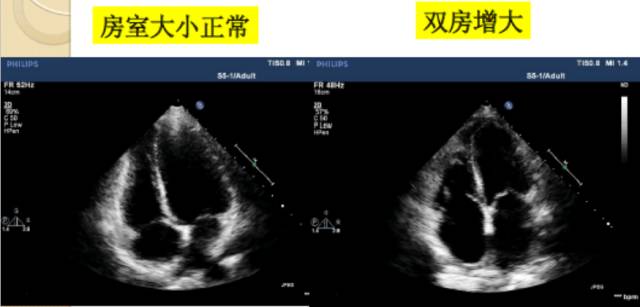

13、右心房的径线测量

测量位置:心尖四腔切面。

测量时相:舒张末期。

右房的长径:从三尖瓣环连线的中点到右房顶部的垂直线。

横径:从房间隔的中部到右房前侧壁的中部。